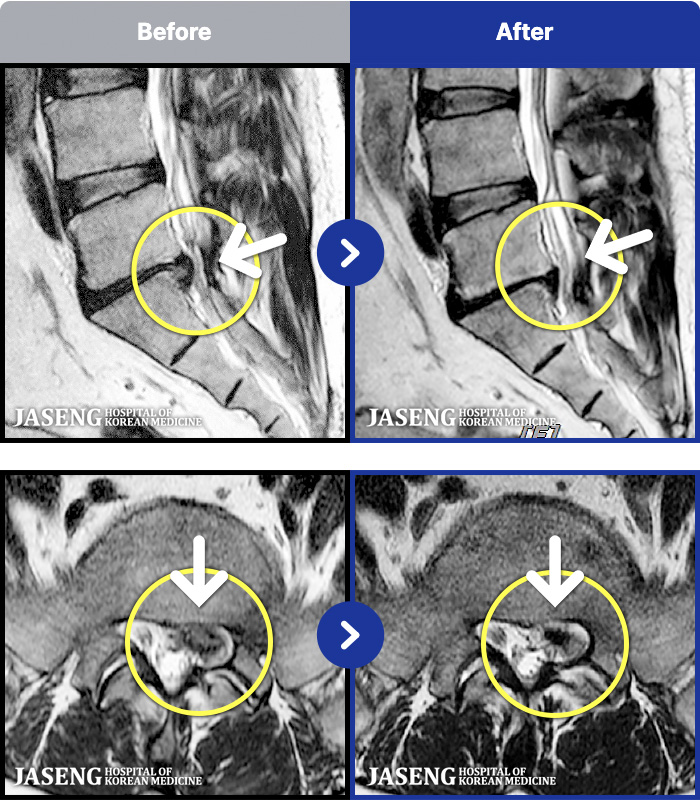

1,286 MRI ũ ʸ Ȯϼ.